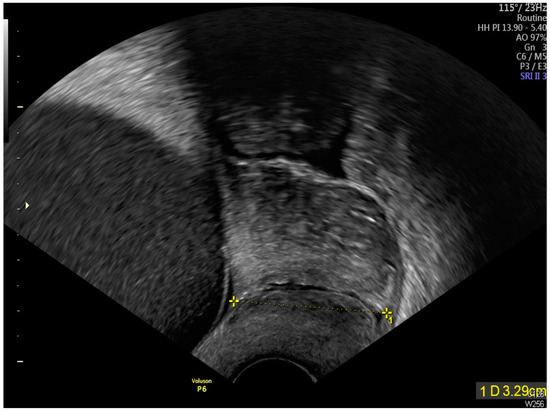

Intrauterine Adhesion-Induced Septated Amniotic Cavity: Ultrasonographic Findings in Second and Third Trimesters

Huang, J.-T.; Chen, Y.-M.; Tsai, C.-C.; Cheng, H.-H.; Lai, Y.-J.; Lee, P.-F.; Hsu, T.-Y.; Huang, K.-L. Intrauterine Adhesion-Induced Septated Amniotic Cavity: Ultrasonographic Findings in Second and Third Trimesters. Diagnostics 2024, 14, 2826. https://doi.org/10.3390/diagnostics14242826